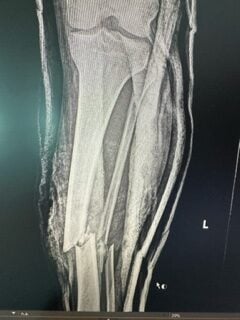

For a brief moment it appeared that Diffut had simply landed feet first, and everything was fine. Then he toppled over, tried to stand, and saw that his left leg was utterly shattered. “I reached down and my foot was bent totally backward [to] where my calf is.” His tibia and fibula were both splintered, sticking out of his skin. “Fragments of my fibula were scattered around the mats,” he said. “It was a horrible image.”

The treatment and surgery, however, were still incredibly brutal. “I had three nurses holding my leg and basically hammering the bone because it wasn’t going back in.” The following day, he underwent surgery. “They opened up my knee, drilled a hole through my shin to my ankle, then put a metal rod down that hole. Where my shin is supposed to be is now a metal rod.”